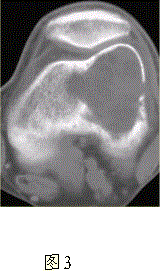

问题 患者女,35岁,左膝关节隐痛1年余,近1周加重,活动后明显疼痛。查体:左股骨下端外侧肿胀,压痛。行左膝关节正侧位CR,并行左膝关节CT扫描,见下图。 根据膝关节CR和CT影像,你认为此病例的影像学表现有

选项 A.左股骨外髁溶骨性骨质破坏 B.病灶呈明显膨胀 C.病变边缘清晰,有明显硬化缘 D.CT示左股骨外髁骨皮质不完整 E.病灶边缘可见骨膜反应,Codman三角形成 F.病灶周围软组织肿胀

答案 ABDF